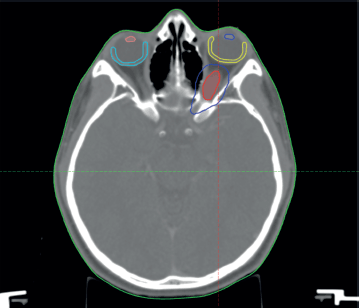

The patient was discussed at a pediatric multidisciplinary tumour board resulting in a recommendation for the patient to be treated with definitive radiotherapy. A computed tomography (CT) scan was done in planning position with the child supine using a headrest and thermoplastic mask for immobilization. The magnetic resonance imaging (MRI) was fused with the planning CT scan to facilitate accurate target volume delineation. The gross tumour volume (GTV) was contoured, and planning target volume (PTV) margin generated with 5 mm outward expansion from the GTV (Figure 2). The prescribed dose to the PTV was 54 Gy in 27 fractions delivered via intensity-modulated radiotherapy (Figure 3). The maximum radiation doses to ipsilateral critical structures such as the left retina, macula, cornea and lens were 52, 43, 46 and 10 Gy, respectively (Figure 4).

Figure 2. Diagram showing the GTV = red, PTV = blue, left macula = yellow, right macula = light blue, left lens = blue and right lens = orange.